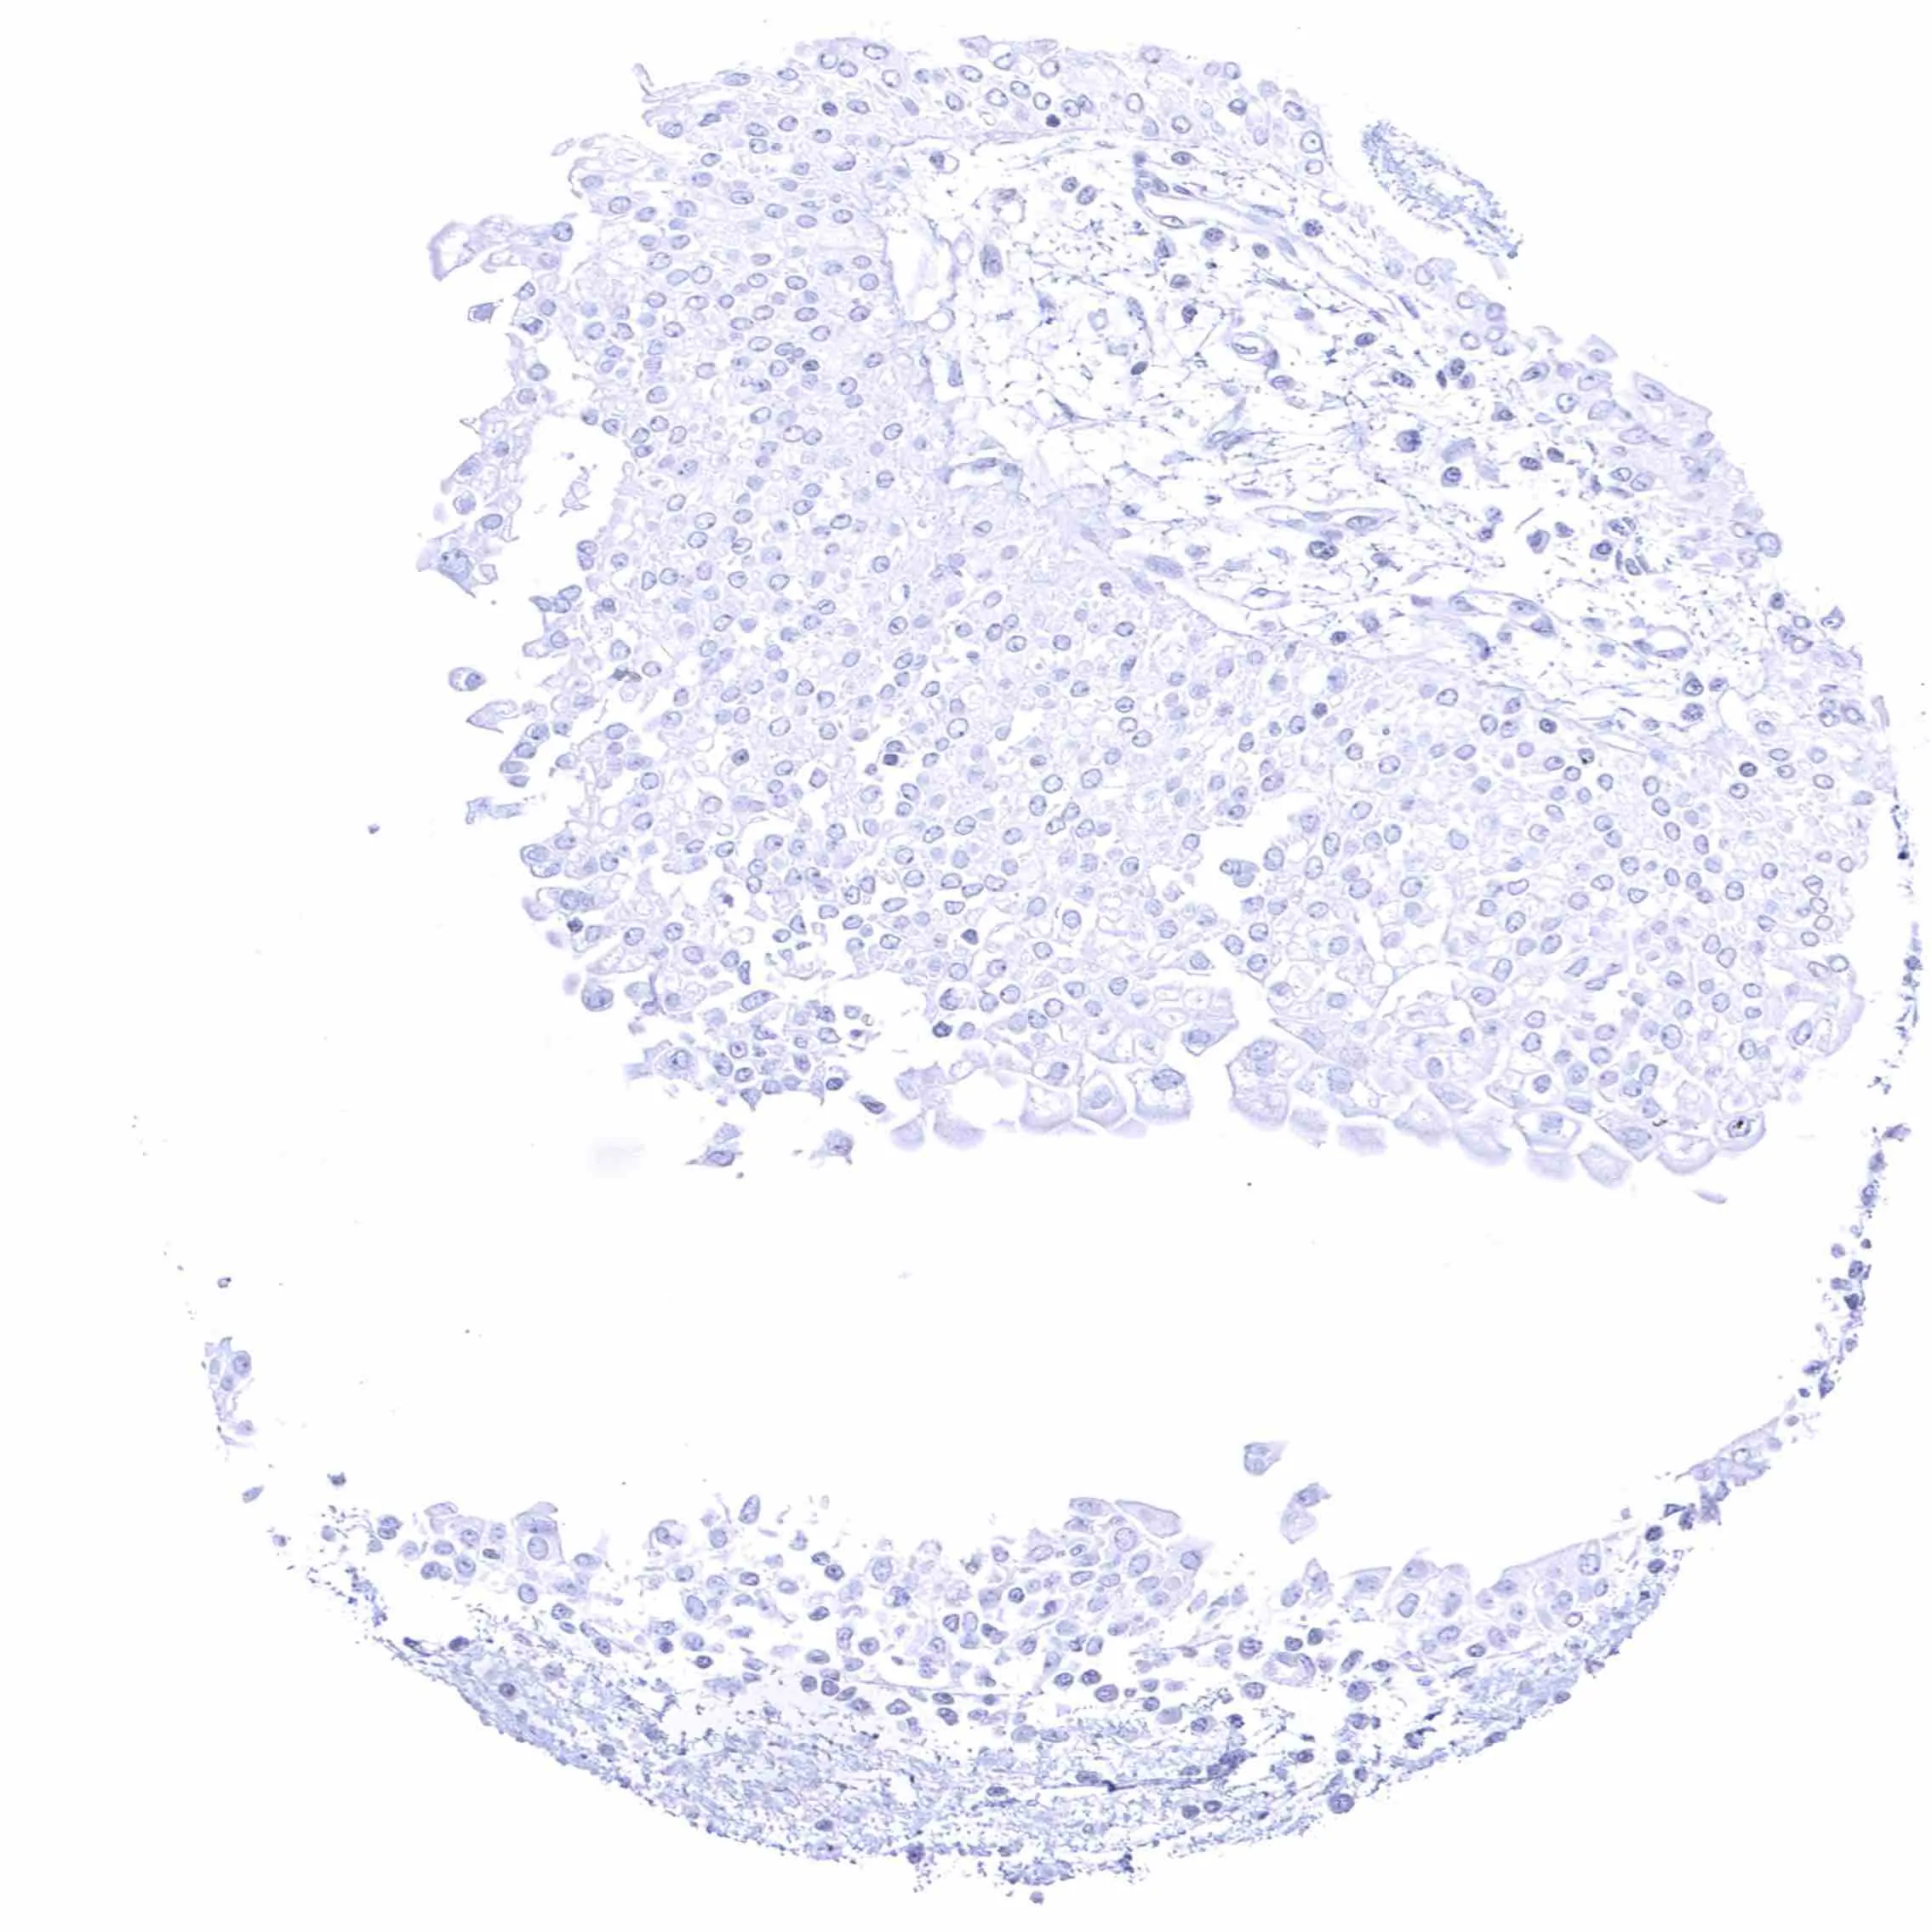

Spleen